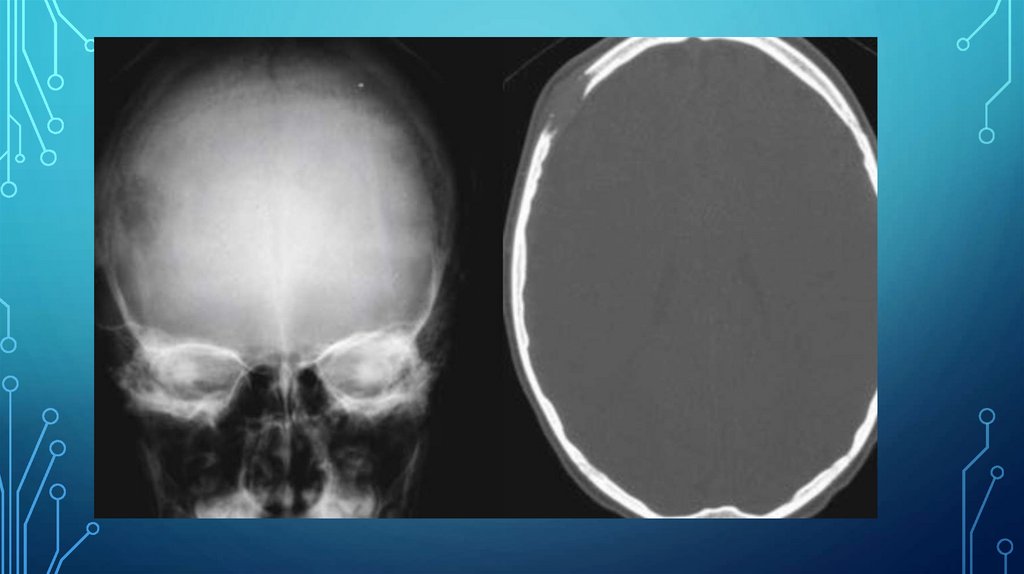

РЕНТГЕНОГРАФИЯ ПОЗВОЛЯЕТ

ОБНАРУЖИТЬ ОЧАГИ ПОРАЖЕНИЯ,

ХАРАКТЕРИЗУЮЩИЕСЯ ДЕСТРУКЦИЕЙ

ПО МЕНЬШЕЙ МЕРЕ 30%

ТРАБЕКУЛЯРНОЙ КОСТИ

ДИФФУЗНАЯ ОСТЕОПЕНИЯ: 85%

МНОЖЕСТВЕННЫЕ ЛИТИЧЕСКИЕ

ОЧАГИ: 80%: - ПРИМЕРНО 1 %

ОЧАГОВ ХАРАКТЕРИЗУЮТСЯ

ОСТЕОСКЛЕРОЗОМ

ЭНДОСТАЛЬНЫЕ ВДАВЛЕНИЯ

МЯГКОТКАННЫЙ КОМПОНЕНТ РЯДОМ

С ОЧАГОМ ДЕСТРУКЦИИ КОСТНОЙ

ТКАНИ

КОМПРЕССИОННЫЕ ПЕРЕЛОМЫ

ПОЗВОНКОВ